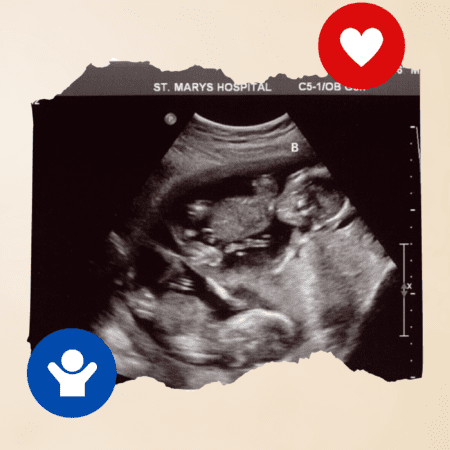

Found my twin at 13 weeks when I went for my first OB appointment. I had 4 scans before that with the IVF dr. Never saw baby B.

∼ DBL

We didn’t find out until Week 21. They missed my Baby B two times prior to that.

∼ MA